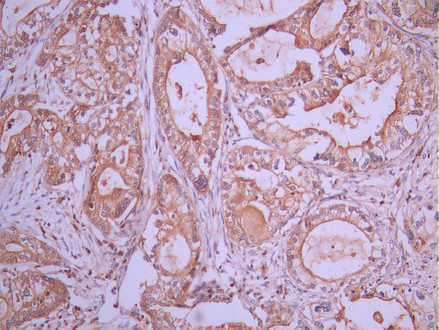

• IHC image of CSB-RA632615A0HU diluted at 1:100 and staining in paraffin-embedded human pancreatic cancer performed on a Leica BondTM system. After dewaxing and hydration, antigen retrieval was mediated by high pressure in a citrate buffer (pH 6.0). Section was blocked with 10% normal goat serum 30min at RT. Then primary antibody (1% BSA) was incubated at 4°C overnight. The primary is detected by a Goat anti-rabbit polymer IgG labeled by HRP and visualized using 0.05% DAB.